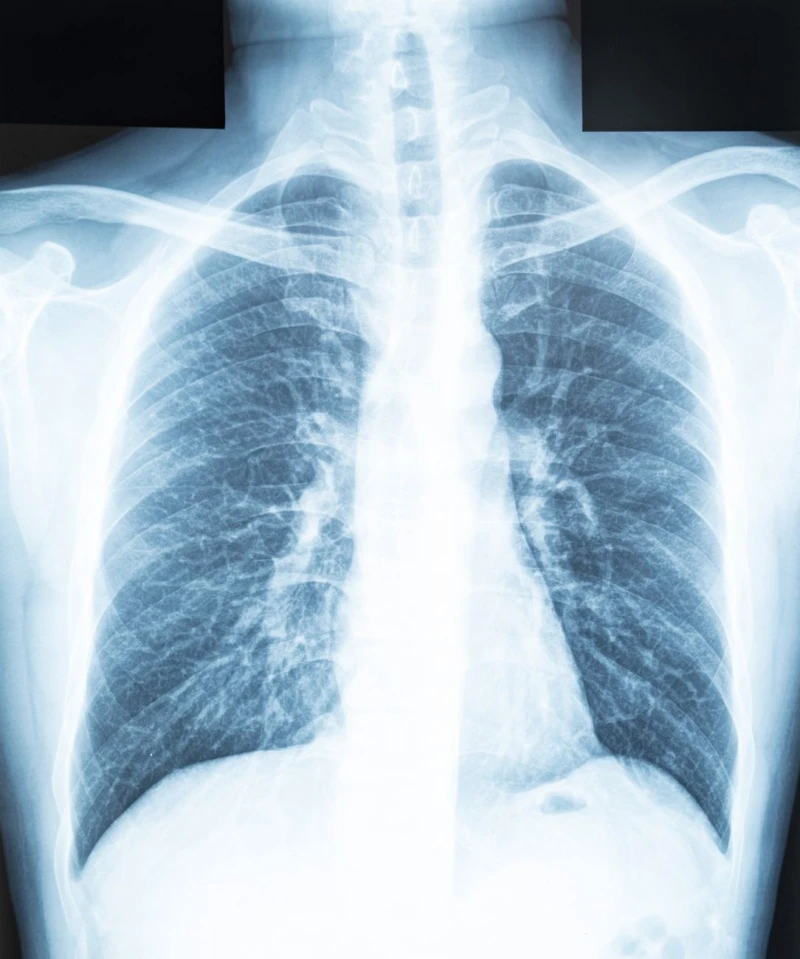

De afdeling Radiologie & Nucleaire Geneeskunde van Franciscus Gasthuis & Vlietland is deze maand live gegaan met “Zorgbericht”. Met Zorgbericht is het mogelijk om beelden en verslagen digitaal te delen met de patiënt. Met deze ontwikkeling is het ziekenhuis een stap dichterbij het uitfaseren van DVD/CD’s.